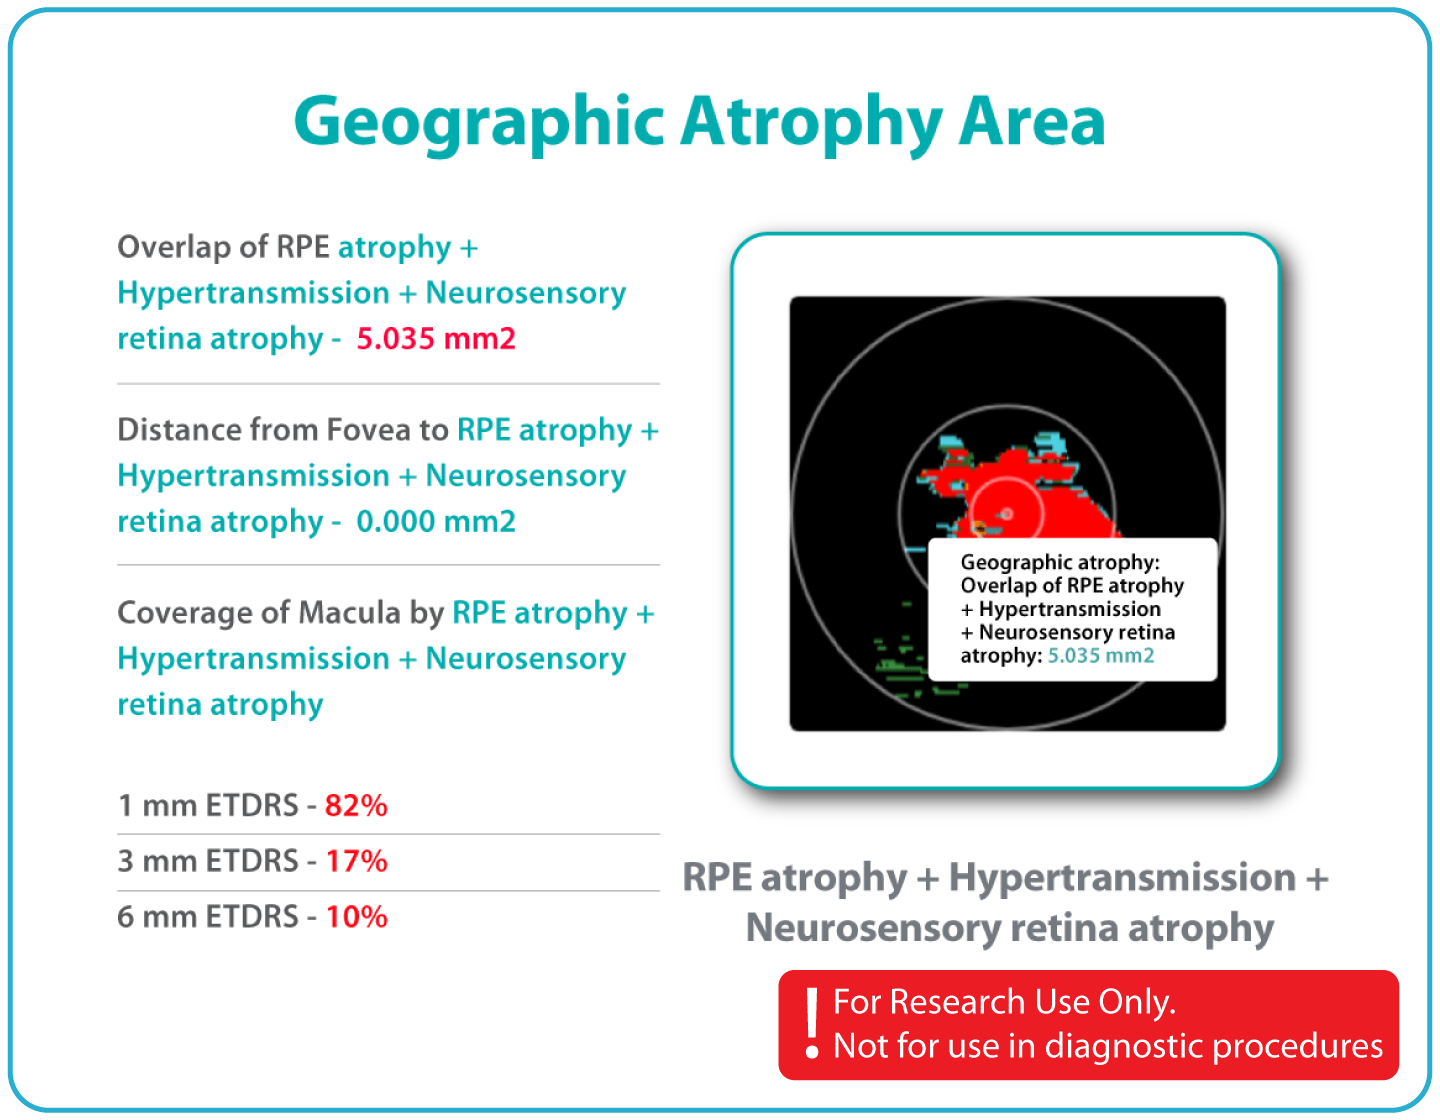

Characterization and visualization of OCT features commonly studied in Geographic Atrophy (GA), including hypertransmission, RPE atrophy, neurosensory retinal atrophy, and EZ changes.

Estimation of GA-related feature areas using combinations of imaging characteristics.

The GA Progression feature provides tools for research-oriented visualization and comparison of OCT imaging data across multiple visits. Users can review changes in areas associated with geographic atrophy (GA) and related imaging features through percentage-based displays, maps, and graphs.

Efficient estimations of GA-associated areas designed to support research-focused image review workflows.

Quantitative, image-derived measurements of GA-related features and associated biomarkers for research analyses.

Visualization of spatial relationships, including the estimated distance between GA-associated regions and the foveal area, as well as macular involvement.

Support for research dataset stratification through calculations based on the overlap of multiple imaging-feature sets. For Research Use Only. Not for diagnostic or clinical decision-making.